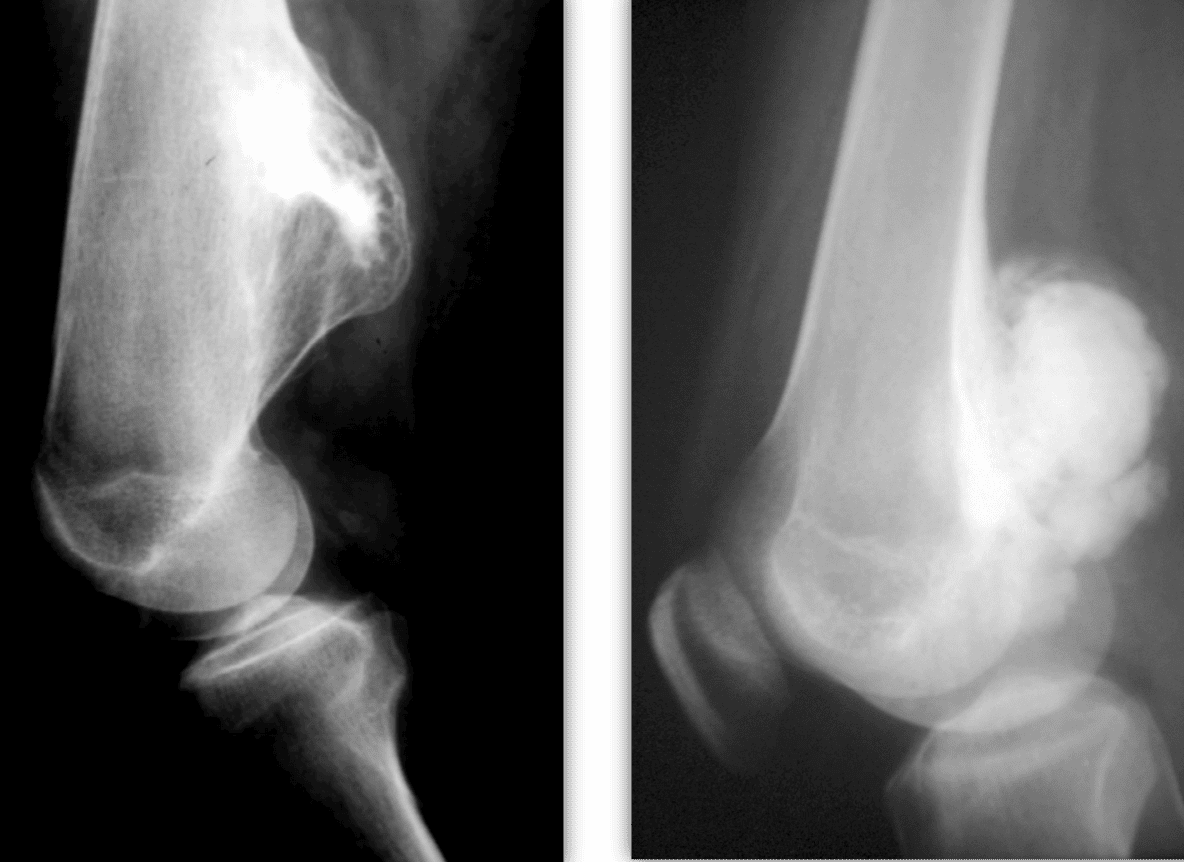

Η απεικόνιση των βλαβών πρέπει να κατευθύνεται από τον Ορθοπαιδικό Χειρουργό και ακολουθεί μία συγκεκριμένη μεθοδολογία.